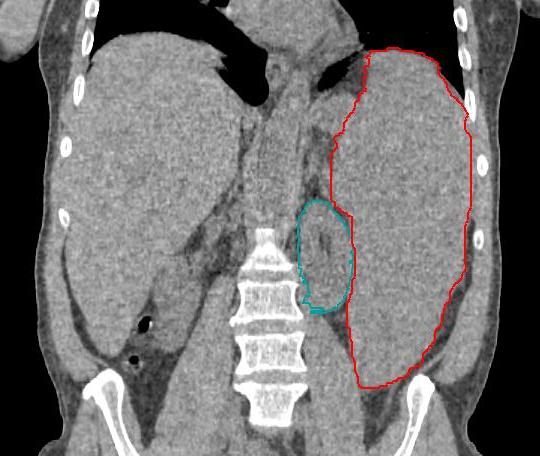

Powiększenie śledziony lub wątroby